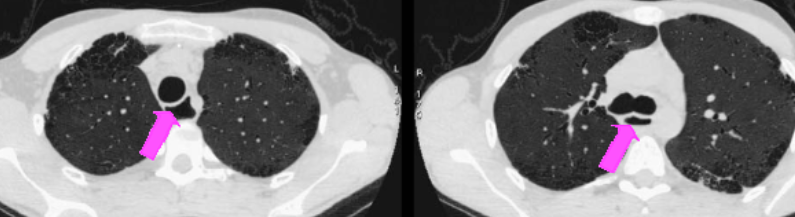

- Fibrose Pulmonaire Interstitielle (NSIP++ ou UIP)

Pattern UIP avec rayon de miel